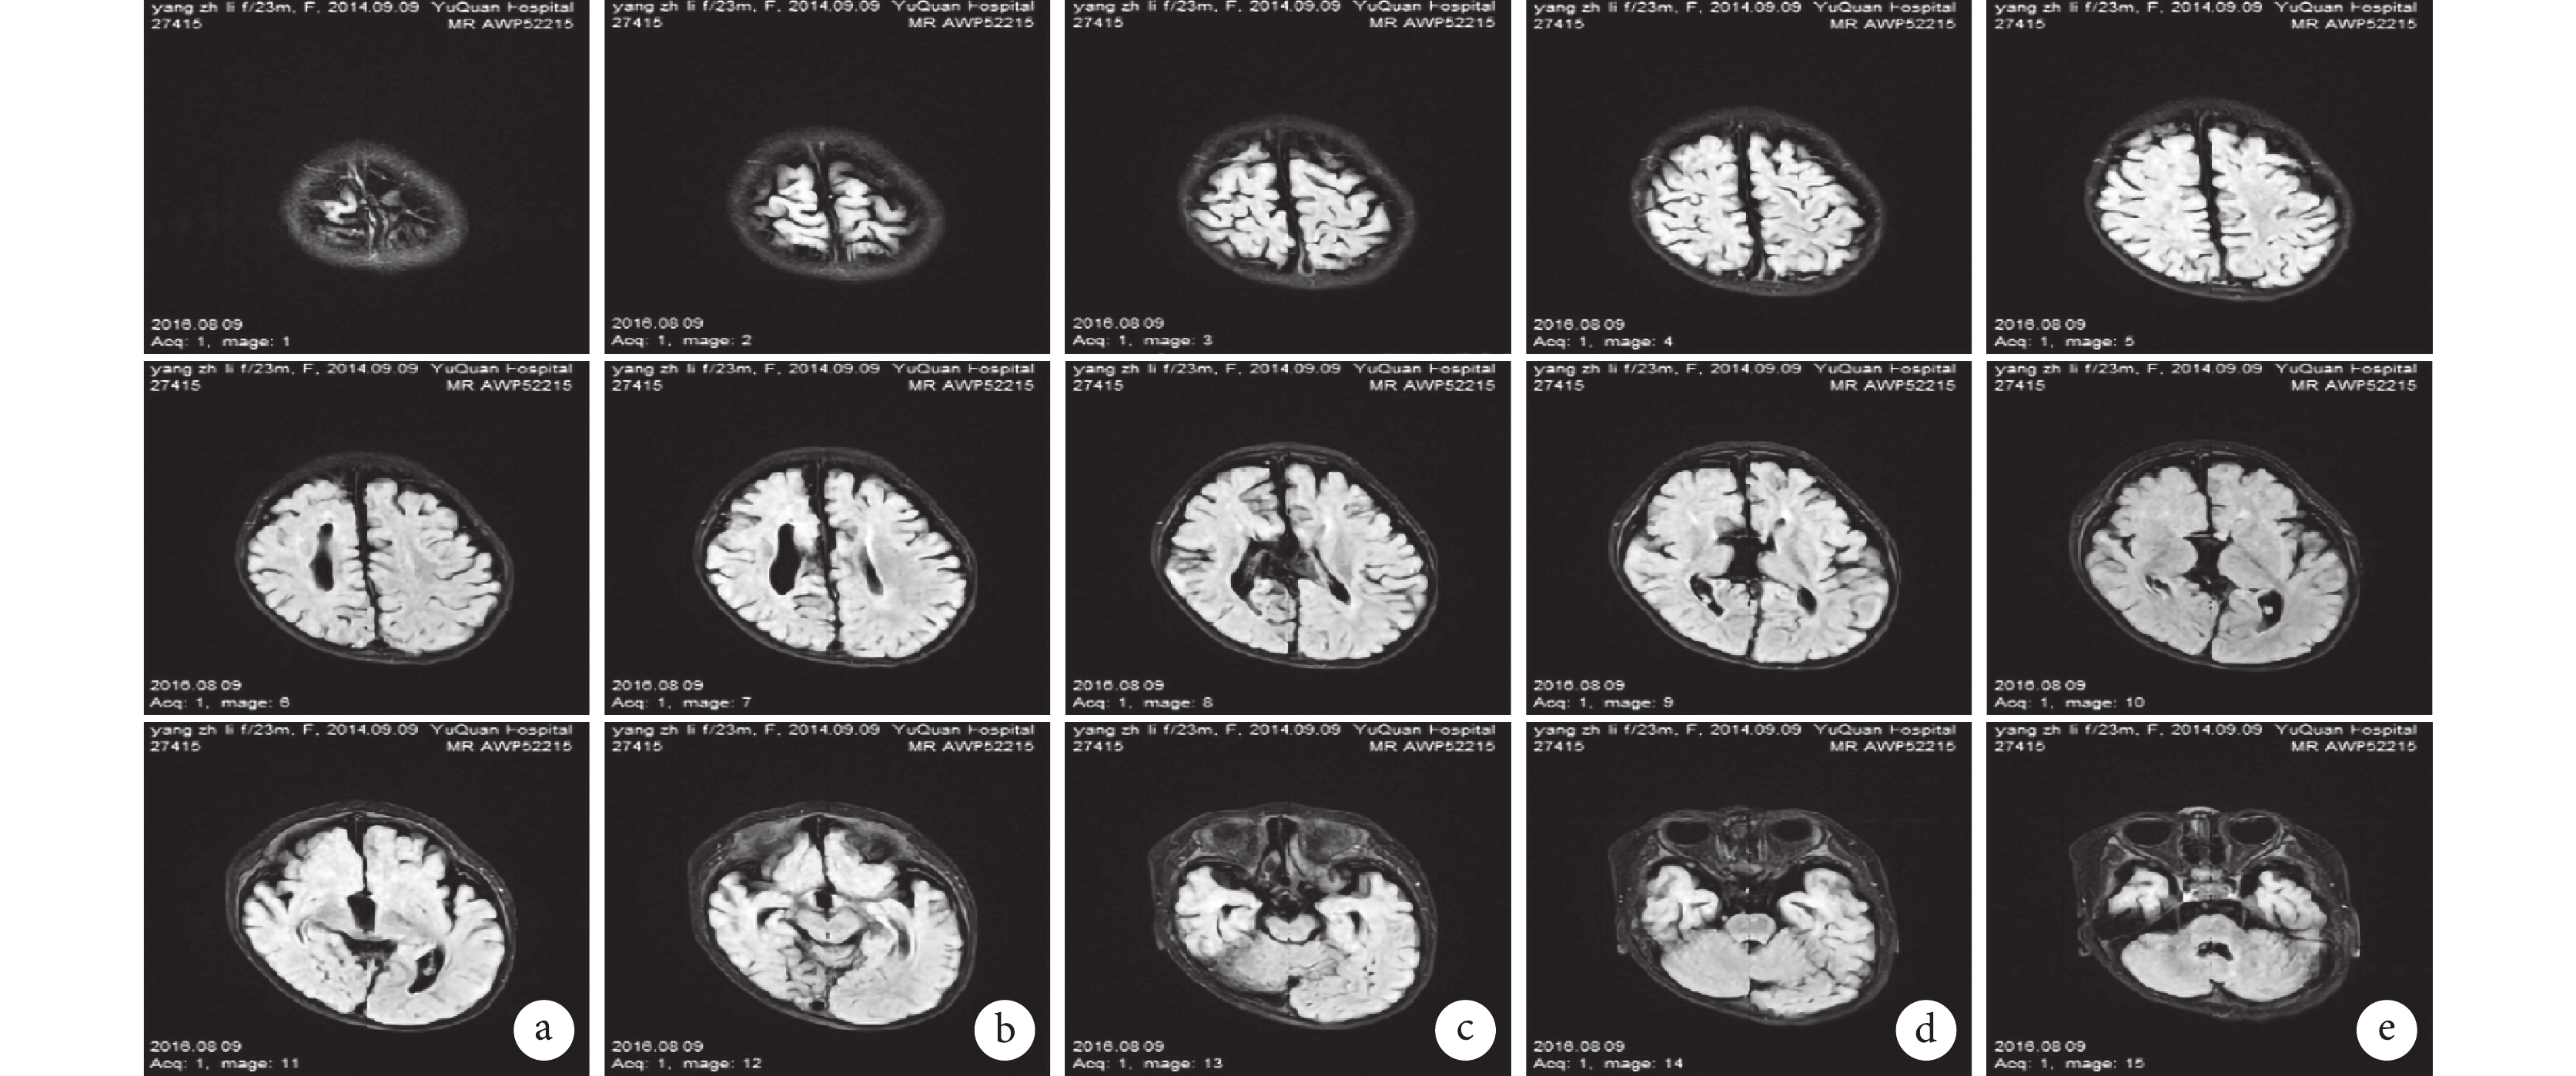

輔助檢查:視頻腦電圖(VEEG)監測示醒睡各期在右半球各導聯可見大量持續性中至高波幅 2~3 Hz 尖-慢波放電,以右側中央-頂、中后顳區為著,左右完全不同步,不對稱,在左側半球各導聯非同步出現較多低至中波幅棘-慢波,多棘-慢波放電、多棘波放電,在監測中記錄到 2 串痙攣發作,四肢快速抖動一下,EEG 表現為:右半球高波幅尖波伴有低波幅快活動→左半球低波幅快活動,持續約 0.5~1.0 s,左右完全分離,并伴有短暫的菱形肌電活動爆發(圖 1)。頭顱核磁共振(MRI)示胼胝體完全缺如,右側額葉多小腦回畸形伴灰質異位(圖 2)。正電子發射計算機斷層掃描(PET-CT)示右側半球代謝減低(圖 3)。

a~c,發作間期:醒睡各期在右半球各導聯可見大量持續性中至高波幅 2~3 Hz 尖-慢波放電,以右側中央-頂、中后顳區為著,左右完全不同步,不對稱,在左側半球各導聯非同步出現較多低至中波幅棘-慢波,多棘-慢波放電,多棘波放電。d~e,發作期:右半球高波幅尖波伴有低波幅快活動→左半球低波幅快活動,持續約 0.5~1.0 s,左右完全分離,并伴有短暫的菱形肌電活動爆發

Figure1. EEG of the patienta~c, IID: large continuous high reflection amplitude 2~3 Hz spike-slow wave discharge in the right hemisphere, mainly appear in right central、parital, temporal regions; low to medium amplitude spike-slow wave in the left hemisphere. d~e ID: low amplitude fast wave in right hemisphere→low amplitude fast wave in left hemisphere. It lasts for 0.5~1.0 s with myoelectricity outburst